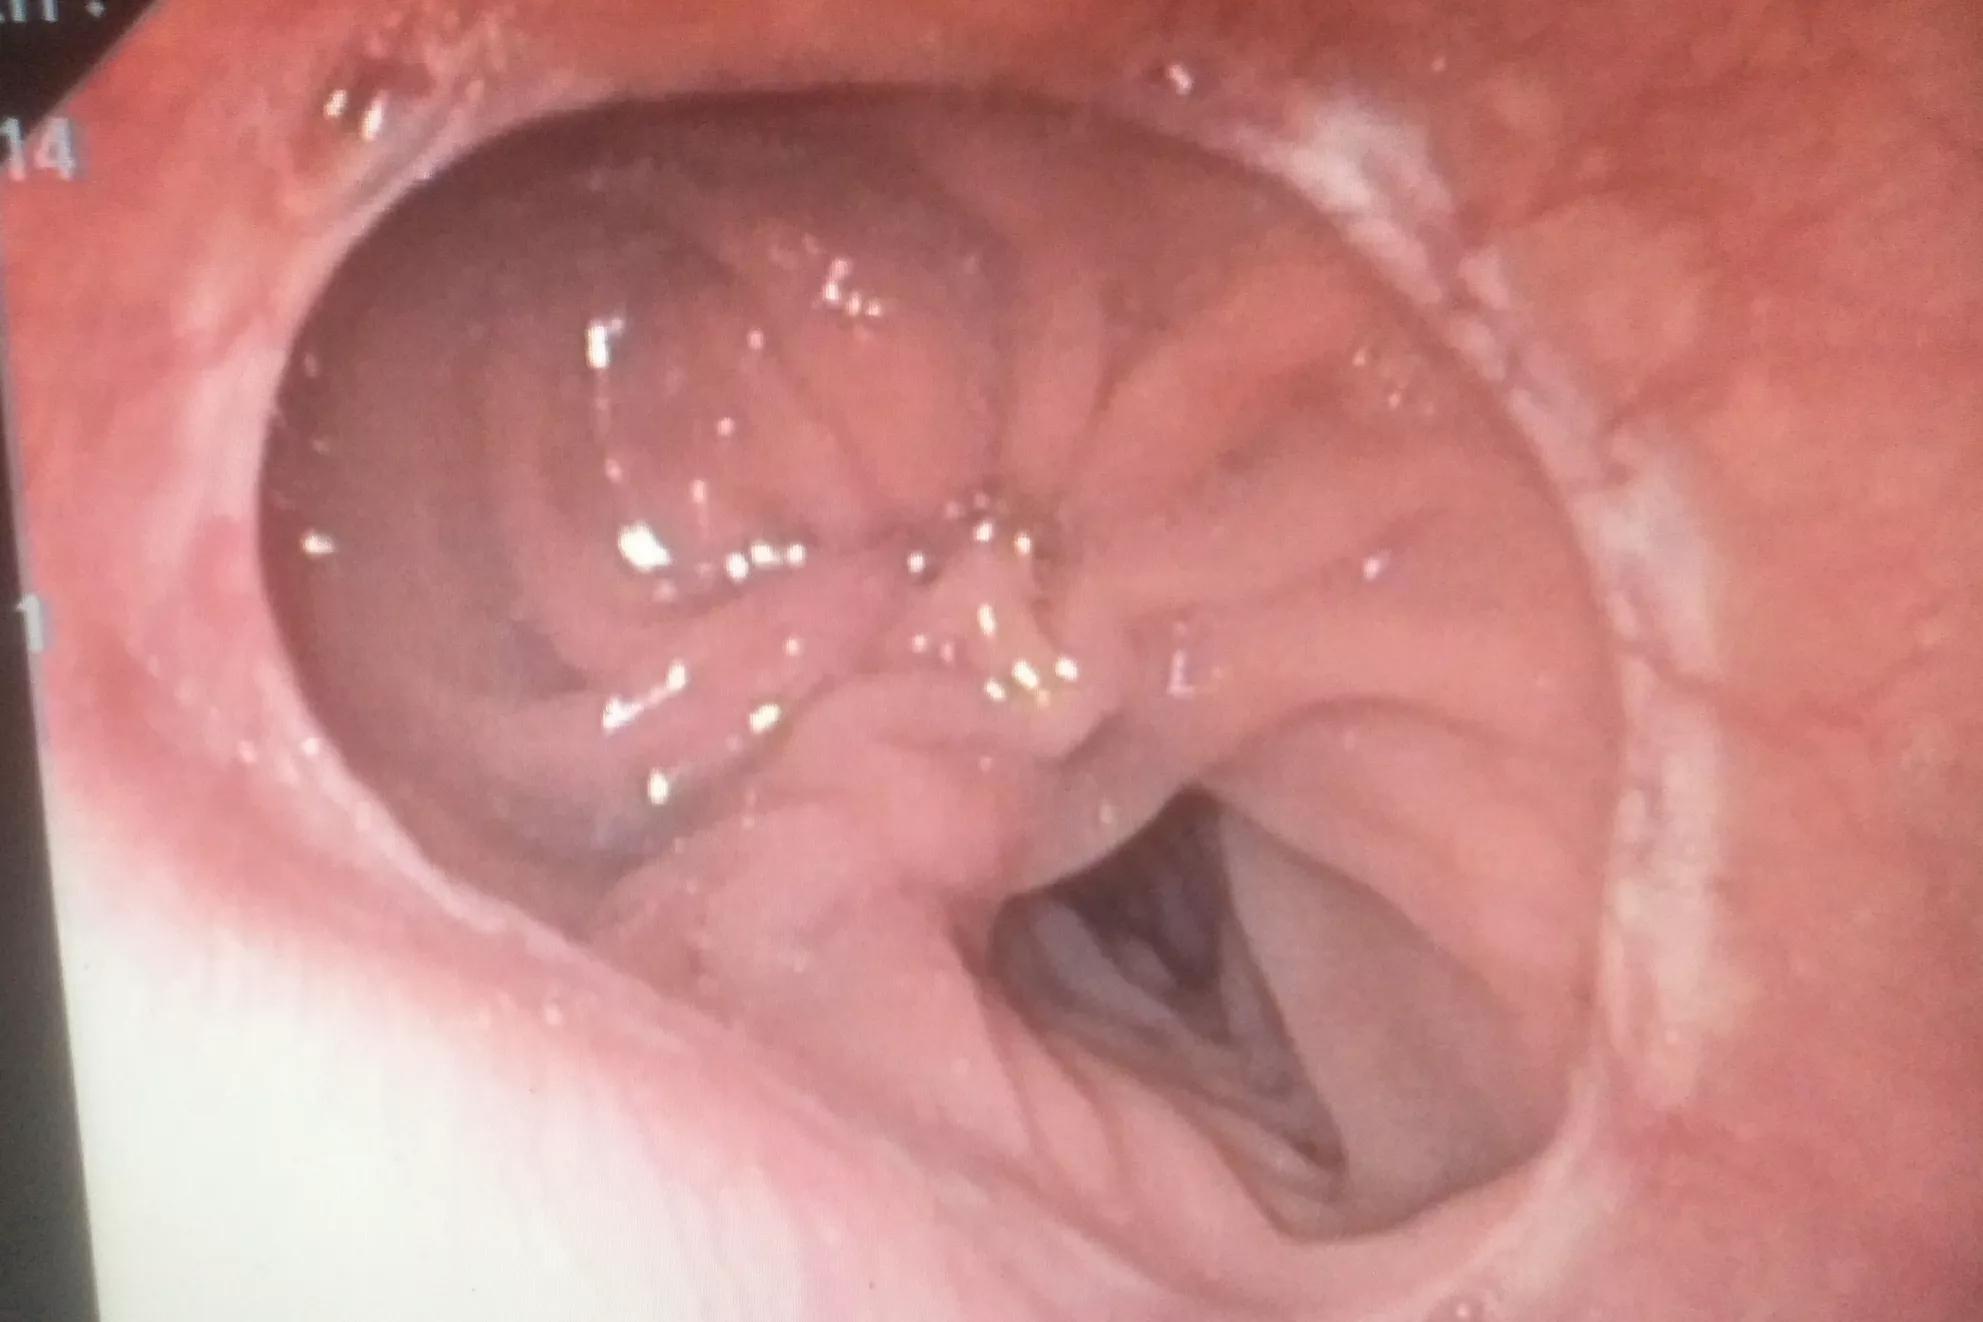

在胃体一胃窦交界处见一直径约3cm的溃疡,溃疡边缘呈锯齿样不整,周边呈围堤样隆起,底部凹凸不平。

检查医生都不相信自已的眼睛,这种溃疡特征怎么可能出现在一个26岁姑娘的身上,因为这种特征显著就是癌性溃疡的特征。一般胃癌起步年龄都在40岁以上,26岁就得胃癌,这在本院胃镜室成立十几年来尚属首次遇到。